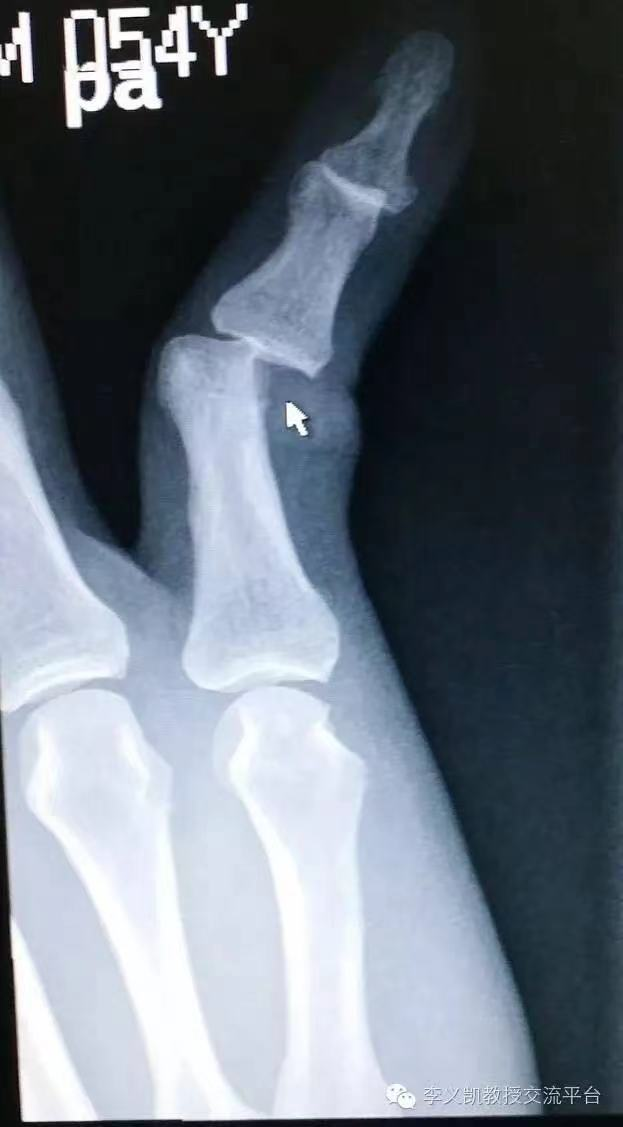

(10)趾骨骨折

趾间关节脱位:足趾弹性固定在某一位置,无骨擦音;X线片可鉴别。